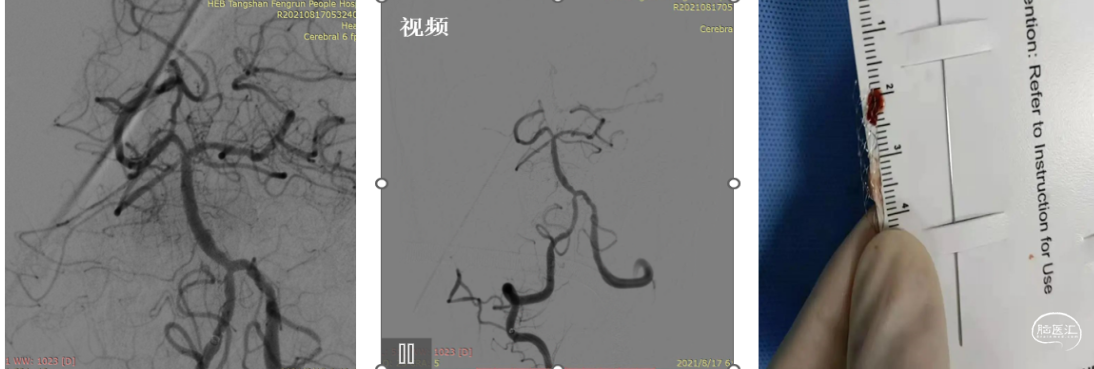

治疗过程影像简述:

导丝携带微导管到达M1段,跟进天巡5F中间导管通过眼动脉段到达M1段。路图下下微导丝到达M2段,跟进微导管,反复来回抽拉微导管捣栓、碎栓。

术中影像简述:

术中造影显示:远端血管再通,推注替罗非班20mL。再次造影显示:M1分叉部狭窄,但血流达到3级,远端显影良好。M1分叉部血管成角明显,球囊扩张可能出现夹层或血管撕裂,血管已达到3级再通,遵循"有所为,有所不为",无置入理念。

患者术后情况:

术后患者意识清,生命体征正常,血压125/80mmHg,言语流畅,肢体肌力5级,病情明显递转,可自行端碗吃饭和肢体活动。

体会:

1.经桡动脉入路的优势适合Ⅲ型弓而经股难以建立通路者。

2.术后患者无需卧床,便于照料。

3.ICAs病变血栓负荷小,可以通过微导管捣栓碎栓实现血管再通,给予替罗非班抗栓治疗。

4.M1分叉部血管成角明显,球囊扩张可能出现夹层或血管撕裂,血管已达到3级再通,遵循"有所为,有所不为",无置入理念。